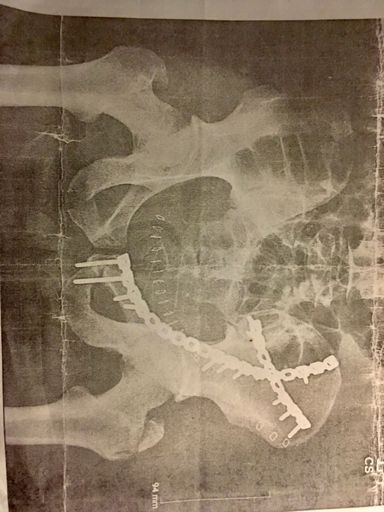

Splitboard Tour - Anniversary of breaking my pelvis